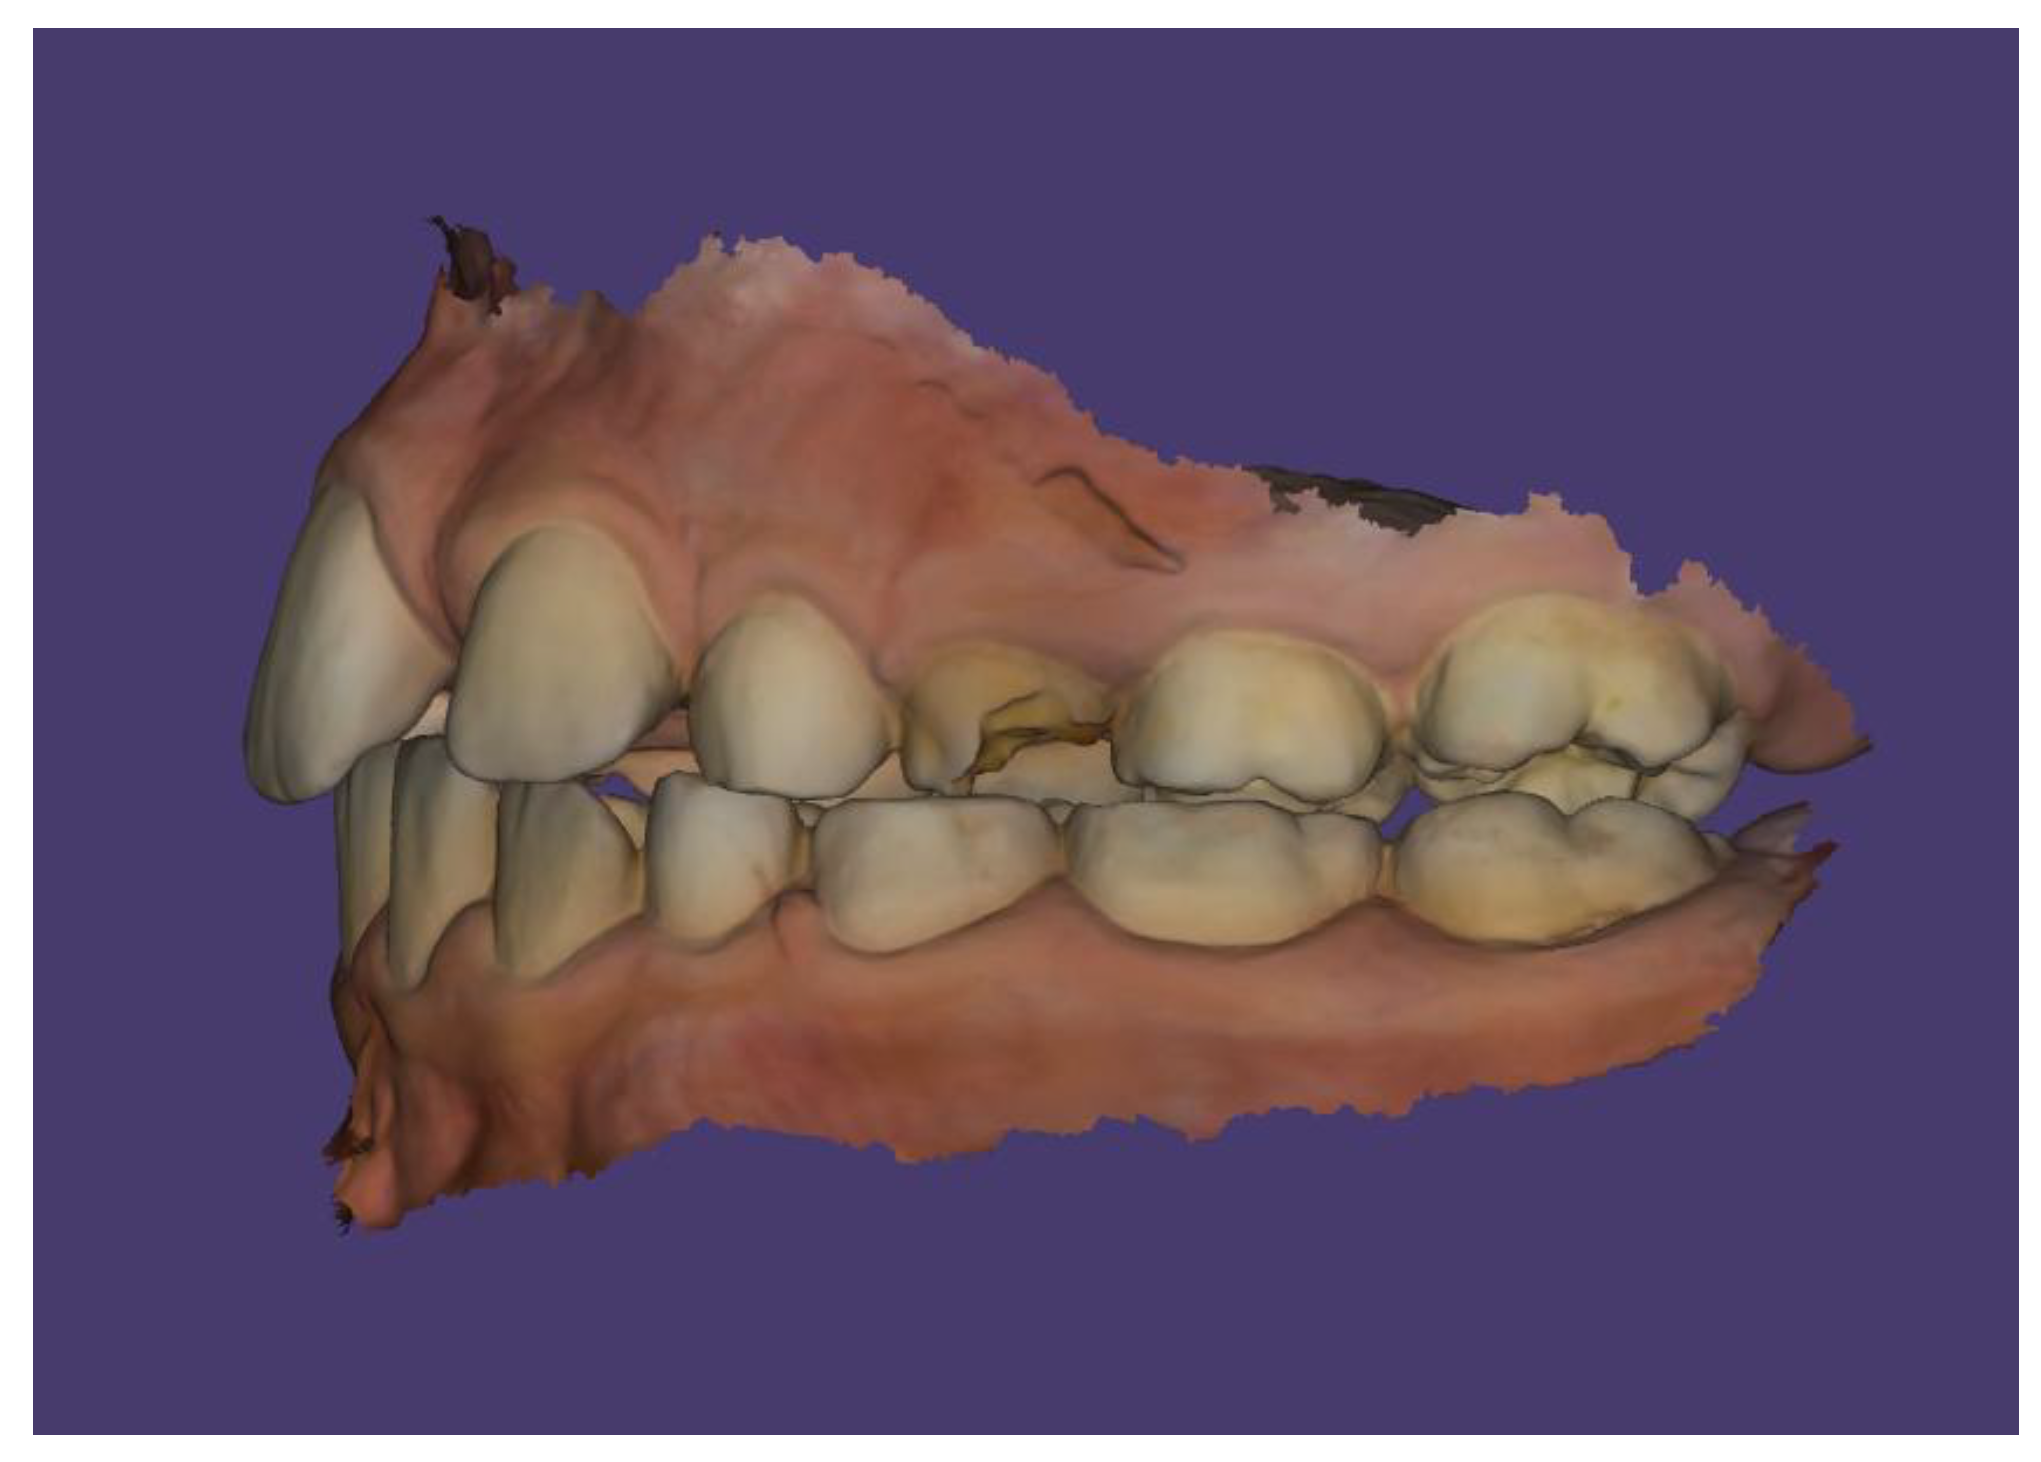

Case Description